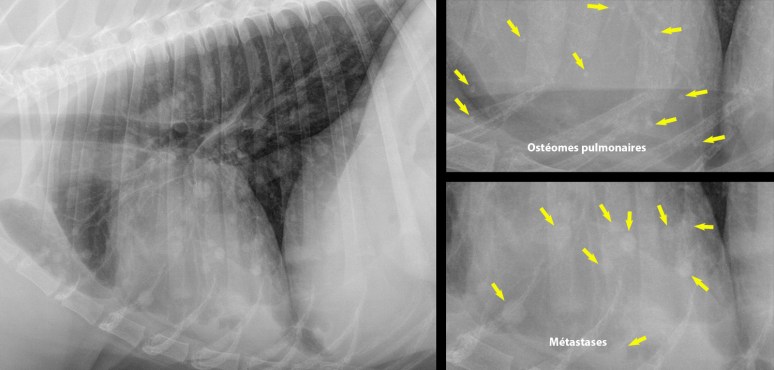

Métastases ? Ostéomes pulmonaires ?

Bien qu’il soit difficile d’écarter définitivement la possibilité de métastases pulmonaires sur les précédentes radios, il n’y avait pas de signe convaincant de nodules de tissu mou. En fait, les multiples petites opacités présentes (en région ventrale surtout) montraient un contour irrégulier et une opacité importante compte tenu de leur très petite taille (1-3 mm), correspondant davantage à des foyers de métaplasie osseuse, ou ostéomes, parfois observés dans les poumons de vieux chiens (grandes races surtout). Ils ont la caractéristiques d’être petits, irréguliers et d’une opacité supérieure aux vaisseaux régionaux de même diamètre. Dans certains cas, il peut être difficile de les différencier des nodules métastatiques calcifiés (un fait rare avec les ostéosarcomes), mais ceux-ci – comme pour la majorité des métastases pulmonaires – montrent une taille plus variable et dont la majorité excède 5mm de diamètre. L’origine de ces ostéomes reste inconnue, mais cette trouvaille est considérée non significative.

Ci-bas, remarquez la différence entre un poumon criblé de nodules métastatiques (tumeur vulvaire épithéliale maligne) à gauche et en haut à droite, de forme bien circulaire, au contour lisse et d’opacité relativement faible compte de leur taille supérieure à 5mm, faisant contraste avec les ostéomes présents dans l’image au bas à droite. Dans un cas comme celui-ci, il peut s’avérer difficile de détecter de véritables nodules lorsque des ostéomes sont aussi présents…